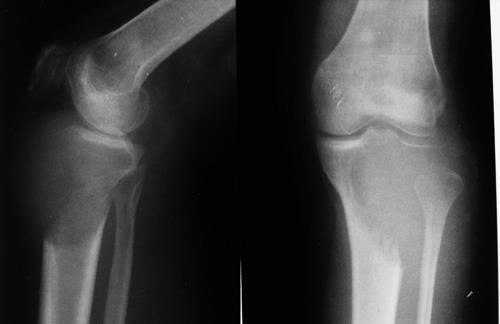

4)骨巨细胞瘤

①20-40岁成人(3/4),10岁以下儿童罕见

②股骨下端最多见,其次为胫骨上端及桡骨下端,三处占全部骨巨细胞瘤的60-70%

③病灶位于骨端,邻关节面(不累及骼后的骨细胞瘤诊断基本不成立)

④病灶延伸至骨突内

⑤手术治疗